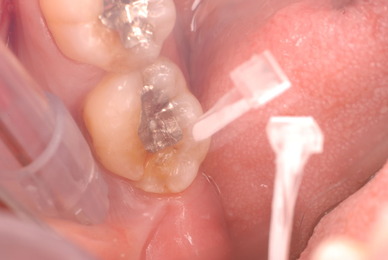

神経が死んでしまった歯は脆いのです。

重症の歯周病で削って上の歯とぶつからないようにしていた歯ですが

いつの間にか神経が死に歯の中が腐っていたようです。

それでヒビが入り割れてしまいました。